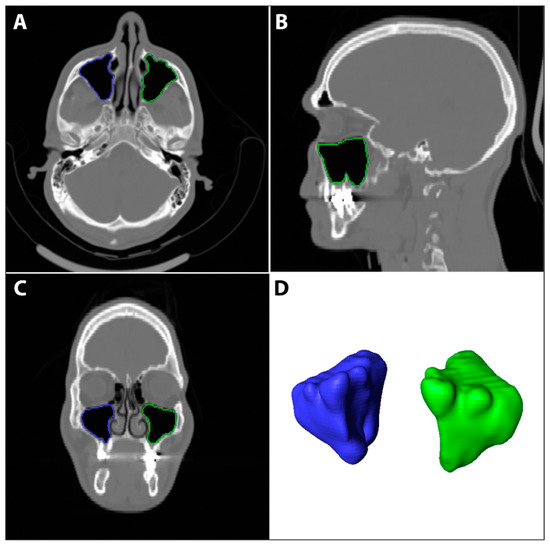

2.3. Evaluating the Maxillary Sinus Volume

The DICOM files’ stack of each scan was imported to Amira software (v. 6.3). The maxillary sinus surfaces (Figure 3) were virtually extracted using semi-automatic and automatic tools. First, to determine the boundaries of the sinuses, the skull was segmented using a threshold tool with masking adjusted to the bone density. Then, in each sinus space, the first, middle, and last slices were marked with the brush tool and interpolated for all slices. Lastly, the sinus surfaces were automatically created using the watershed tool and a gradient image. Unrelated parts (such as the infundibulum) were cleaned from the surface using the lasso tool. The left and right maxillary sinus volumes (L-MSV and R-MSV) were automatically calculated (in cube millimeters) from each sinus surface, using the ‘Surface Area Volume’. An average sinus volume variable was calculated using (RMSV + LMSV)/2.

Figure 3.

The right and left maxillary sinuses were segmented using Amira software (v. 6.3) using automated and semi-automated techniques. Using the brush and the interpolation tools, each sinus was marked on the axial (A), sagittal (B), and coronal (C) views and then a surface was generated from the 3D segmentation model (D). The volume (mm3) of each sinus was calculated from the surface using the ‘Surface Area Volume’ module.

The maxillary sinus volume was divided into three groups, as follows: “Small”: volume < 12 cm3, “Medium”: volume > 12 cm3, and <16 cm3, and “Large”: volume > 16 cm3.